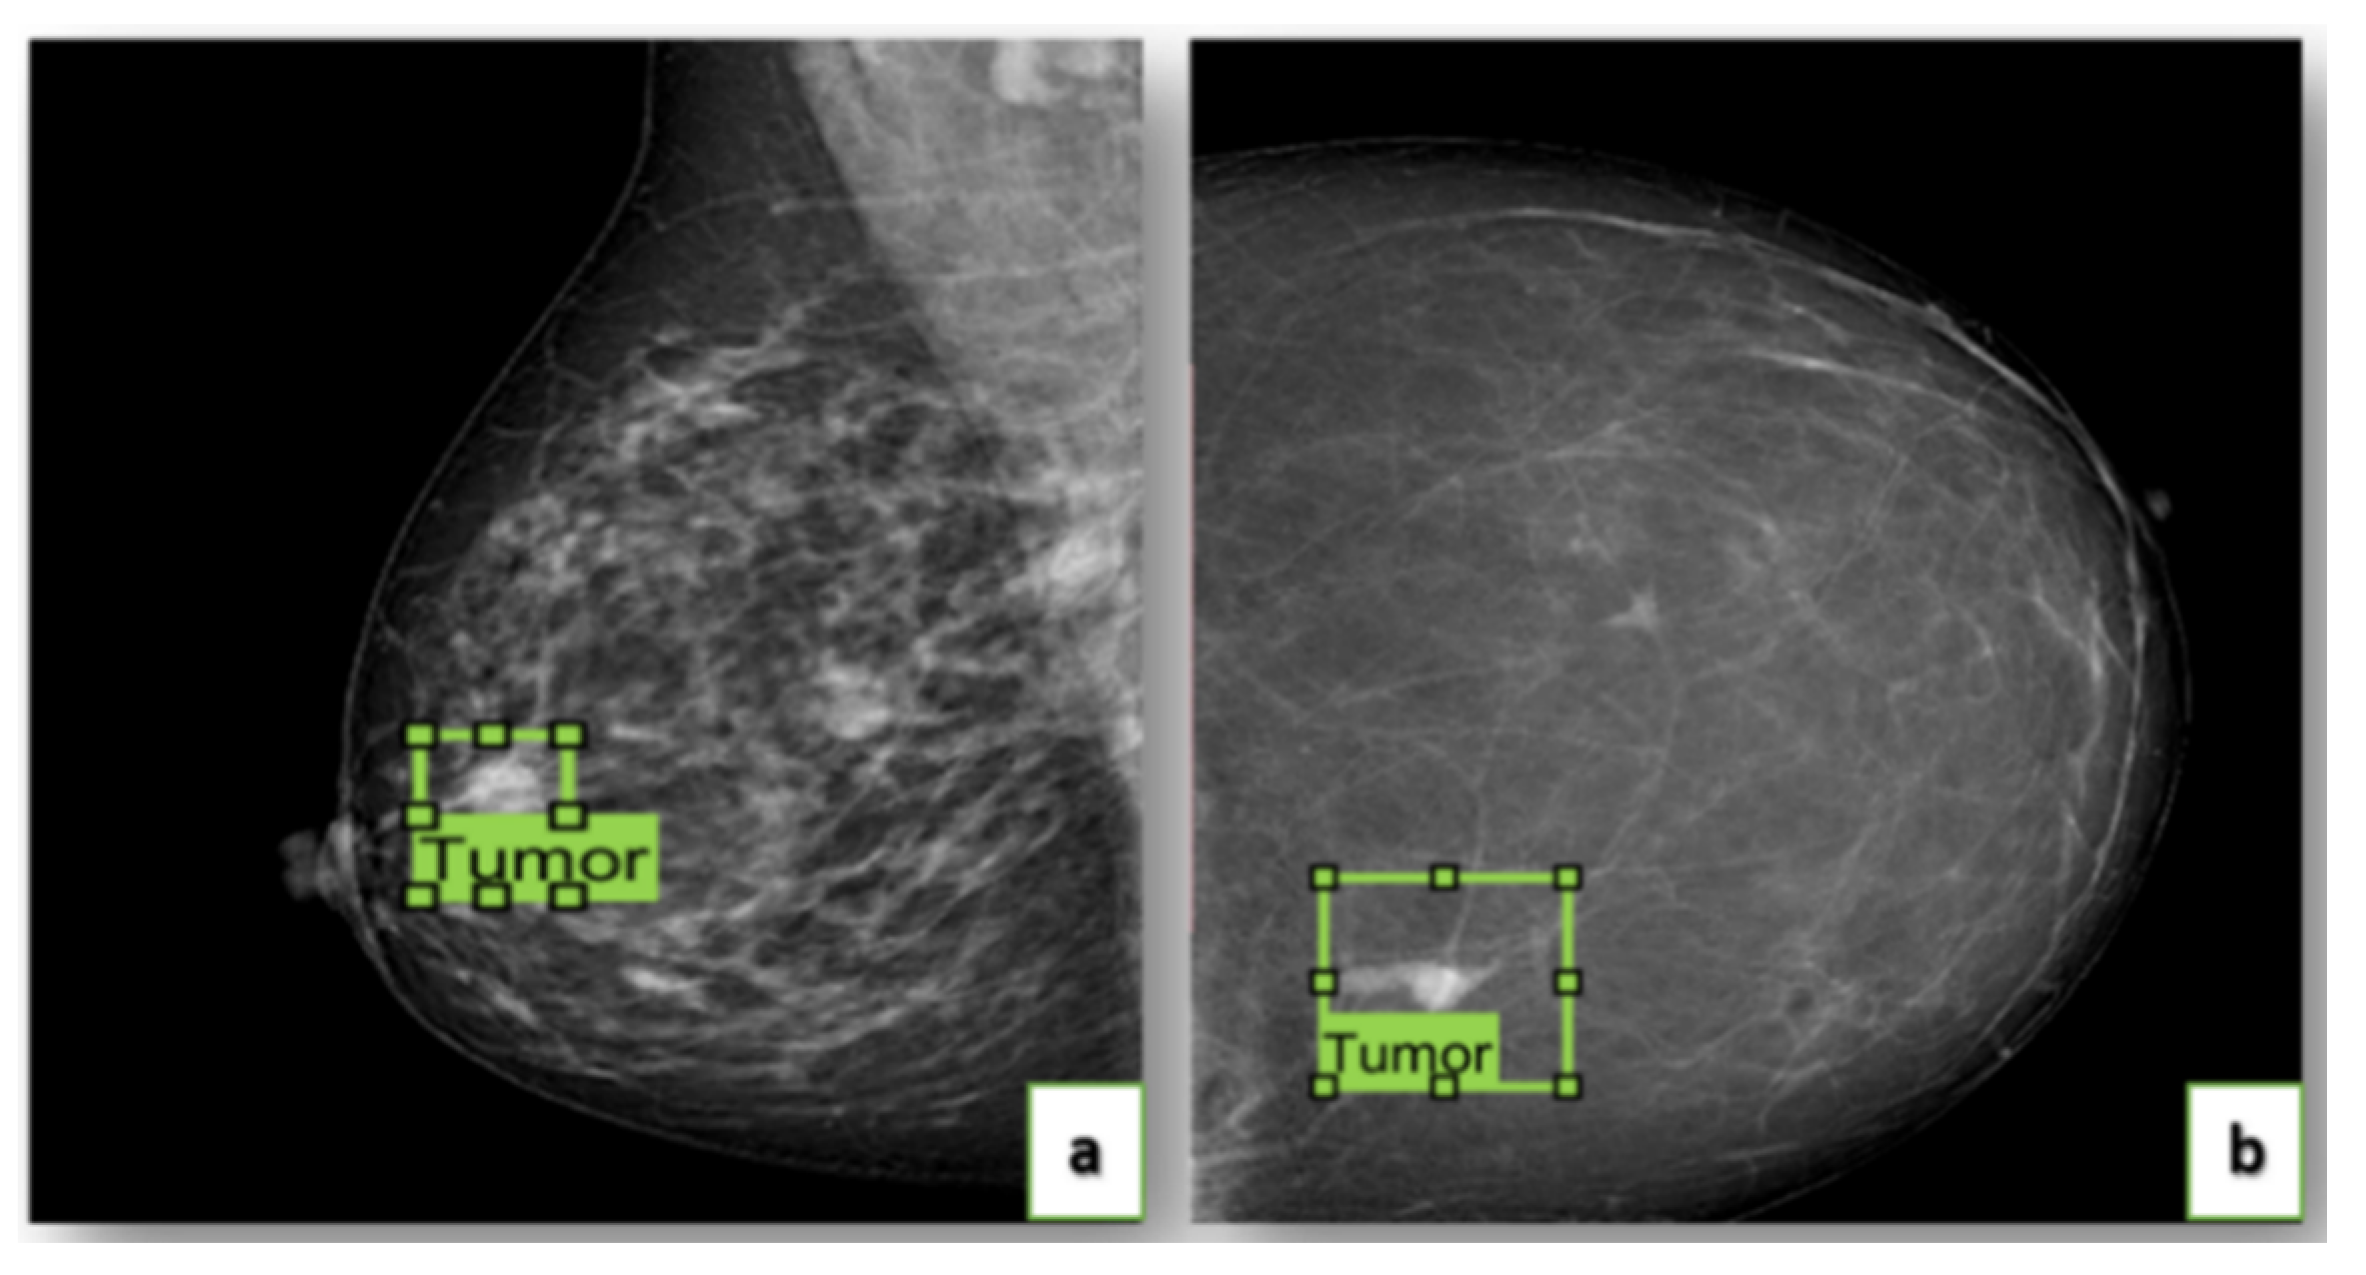

4.2. Annotation of Images

- Image labeling.

- Image validation by a committee of radiologists.